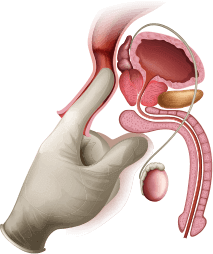

понижувачки медицински процедури

Откако ќе навлезат во телото,

активните компоненти

започнуваат да

дејствуваат

веднаш, елиминирајќи ја болката

и воспалението на клеточно ниво,

отстранувајќи ги

мускулните грчеви, елиминирајќи

ги тромбите и заздравувајќи ги мукозните мембрани.

Активните компоненти на формулата

ја обновуваат стеснетата

уретра.

Па така доаѓа до редовно и комплетно

празнење на мочниот меур.

Нема веќе ноќни посети на тоалетот,

нема веќе болка и непријатност.

Заразените клетки и органи

на генитоуринарниот систем повторно ја враќаат

нивната нормална функција.

Обновување на

циркулацијата на крвта во карлицата.

Обновување

на сексуалната функција.